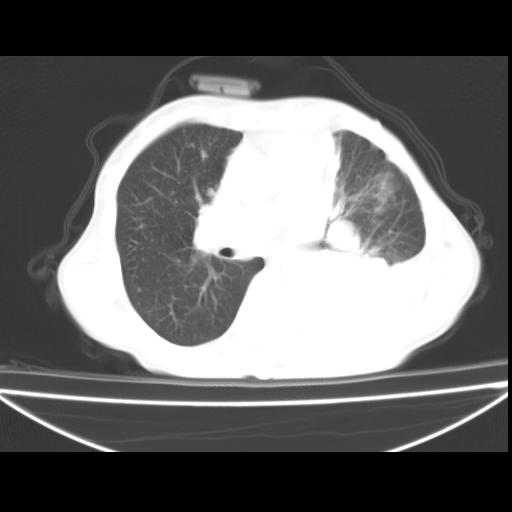

以下是引用随光逐影在2010-3-24 19:15:00的发言:[br]结合病史,考虑双肺及纵隔淋巴结多发转移、左侧胸膜转移并左侧大量胸水,左下肺膨胀不全。

以下是引用zxl51642在2010-3-24 18:49:00的发言:[br]结合乳腺癌术后病史,考虑双肺及纵隔淋巴结多发转移、左侧胸膜转移并左侧大量胸水、左下肺膨胀不全。